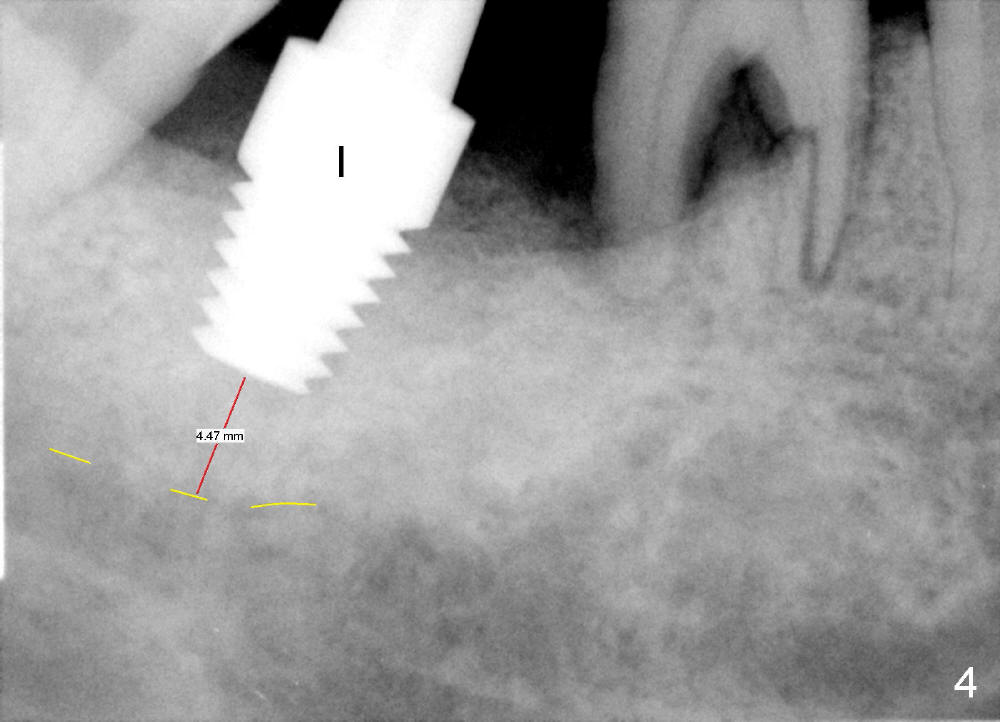

Luckily the patient returns for #31 implantation 4 months post socket preservation. Bone forms in the alveolus and above (Fig.1 black and white arrowheads, respectively). A 6 mm tissue punch is used to open the wound (Fig.2). Osteotomy forms using bone expanders, reamers and taps (Fig.3: 6x14 mm tap). Without infection, local anesthesia is more easily achieved than immediate implant when infection exists. The depth is controlled more readily with delayed implantation. Following adjustment of trajectory, a 7x11 mm implant is placed with insertion torque 60 Ncm (Fig.4 I). Fig.5 shows that the implant obliterates the wound; an abutment (A) is placed to retain perio dressing. With formation of new bone from socket preservation, insertion torque seems to be more easily obtained with the short implant. There is no space to re-use the harvested bone (Fig.6). The implant remains stable postop. Apparent new bone is forming toward the distal coronal threads 5 months postop (Fig.7). The bone around the implant remains stable 17 months post cementation (Fig.8), although there is an episode infection at the neighboring tooth (#30). The patient is more eager to have implants for the maxilla, since the flipper has lost. After implant placement at #7, the pain at #30 becomes more severe.